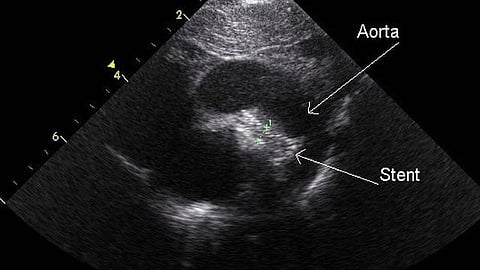

Angiography has limitations, however, making it difficult to determine the true artery size and the makeup of the plaque, and is suboptimal in identifying whether the stent is fully expanded post-PCI and in detecting other conditions that affect the early and late outcomes of the procedure. Intravascular ultrasound was introduced more than 30 years ago to provide a more accurate and specific picture of the coronary arteries. Even though studies have shown that IVUS-guided PCI is superior to angiography-guided PCI and reduces cardiovascular events, it is only used in roughly 15 to 20 percent of PCI cases in the United States, since the images may be difficult to interpret and the procedure is not fully reimbursed.

Optical coherence tomography uses light instead of sound to create images of the blockages. OCT images are much higher in resolution, more accurate, and more detailed compared to IVUS, and easier to interpret. However, as a newer technique, OCT is used in only 3 percent of PCI cases, partly because of a lack of study data—a limitation this new study has addressed.